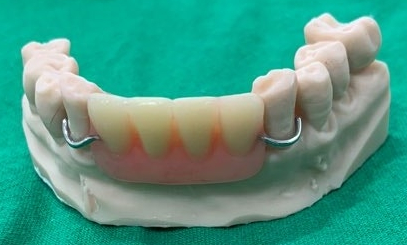

아래 앞니는 ‘플리퍼’라 부르는

꼈다 뺐다가 가능한 보철을 사용하고 계셨는데

아무래도 자연치처럼 붙어있지 못하고

들썩거리기도 하며

꾸준히 관리를 해줘야 되니

번거롭고 힘드셨다 합니다.

임플란트를 심고 나서

바로 올려드릴 수 있는 보철을

만들고 있는 모습인데요,

T 마커 덕분에 디자인이

아주 예쁘게 잘 나왔습니다.

픽스처를 심은 당일에

그 위로 바로 어버트먼트를 연결해 드렸고

그 위로 임시치아까지

올려드렸습니다.

주변 자연치와 유사한 색으로

자연스럽게 만들어드렸으며

위쪽(교합면)에서 바라보면

이렇게 보이는데

이전의 플리퍼와 달리

어버트먼트에 살짝 기대어 올려드렸기에

훨씬 더 고정력이 있고 편하실 겁니다.